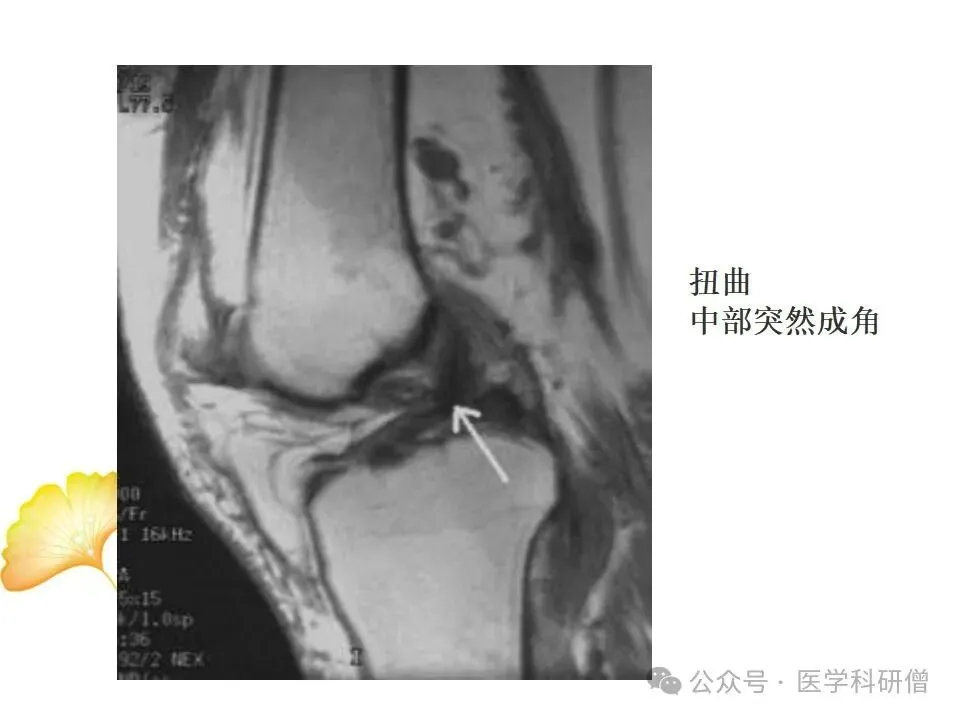

MRI是一种先进的医学成像技术,能够提供高分辨率的膝关节图像,对韧带损伤的诊断具有重要价值。MRI检查可以采用不同的成像技术,如:

通过这些技术,医生能够准确判断韧带的损伤类型、程度和范围,从而制定出合适的治疗方案。